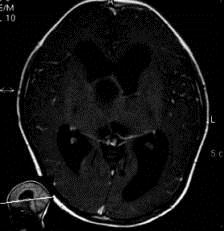

问题 病历摘要:??患者女性,6岁,半年来感觉视力模糊,近10天出现反复头痛,间有恶心呕吐,精神转差,查体:神志清楚,身高90cm,体重25Kg,血压90/55mmHg,右眼视力4.6,左眼视力4.8,双侧视乳头水肿,颈软,伸舌居中,四肢肌张力正常,肌力5级,双侧Babinski征(-)。 手术利用右侧翼点入路,在显微镜下利用鞍区自然间隙进行,一般来说,第二间隙可以窥见的结构有?

选项 A.右侧视神经 B.右侧大脑前动脉 C.前交通动脉 D.垂体上动脉 E.Heubner?回返动脉 F.颈内动脉床突上段 G.基底动脉 H.右侧小脑前下动脉

答案 ADFG

解析 ADFG